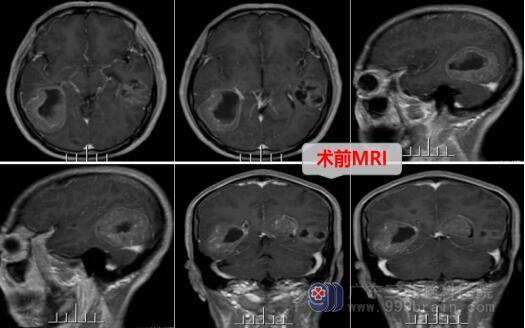

外出打工的孩子知道父亲身体不适后急忙回到家中,陪谢叔到当地医院就诊,查头颅MR示“颅内多发占位性病变,考虑转移瘤”,后行PET/CT示“1、左肺上叶尖后段结节状高代谢病灶,考虑为左肺上叶周围型肺癌;2、右侧额叶、右侧枕叶及双侧颞叶多个不规则囊状低密度兆,考虑为多发脑转移”。

欧阳辉教授结合患者的临床症状和检查结果,考虑为肺癌脑转移瘤。神经外十科医疗团队经过讨论后,决定为患者实施手术切除颅内的肿瘤,术中肿瘤成功切除,病理结果提示为右侧颞枕叶转移瘤-考虑肺腺癌转移。术后,患者还需要针对肺癌原发灶等进行综合治疗。